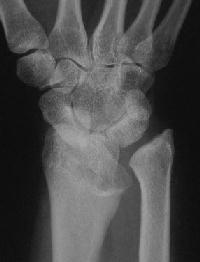

Case 1. Typical Xray findings of congenital Madelungs.